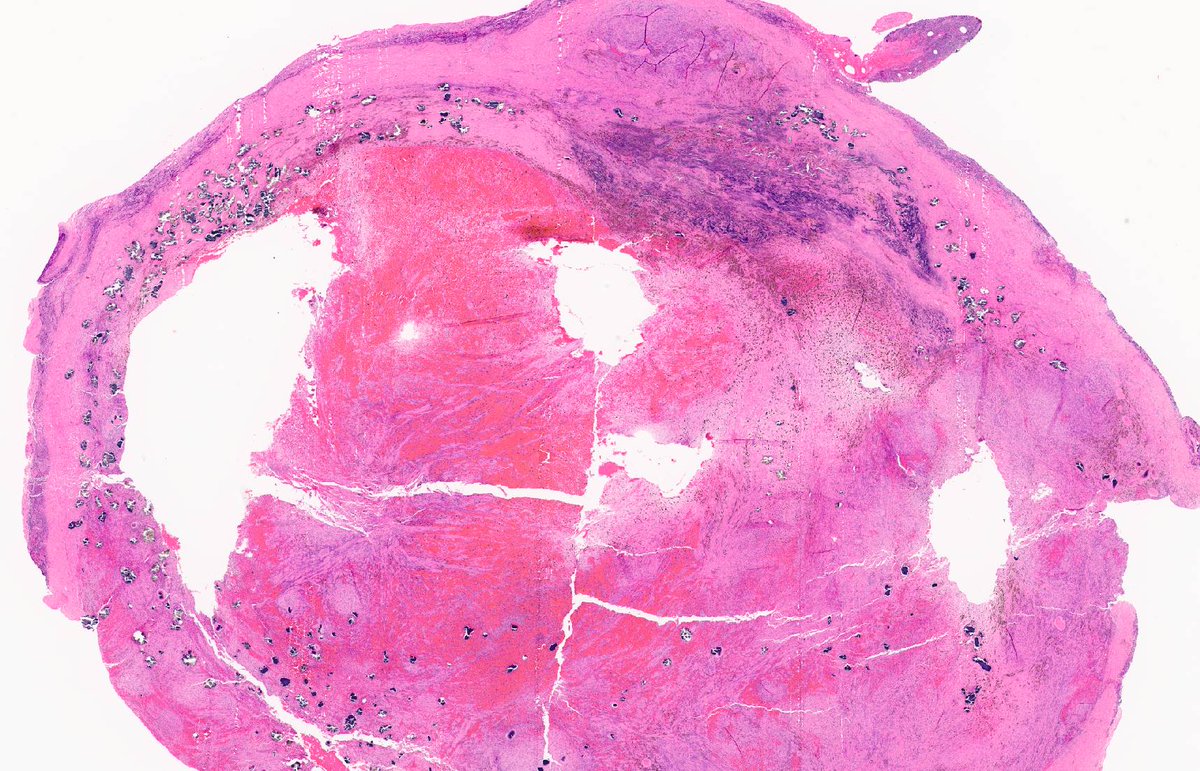

INTRANODAL PALISADED MYOFIBROBLASTOMA. IHC: SMA. NB: circumscribed with peripheral lymphocytic cuff; fascicles of spindle cells; bland nuclei with vague palisading; interstitial haemorrhage / haemosiderin; 'collagenous bodies' with variable mineralization.

1

39

123